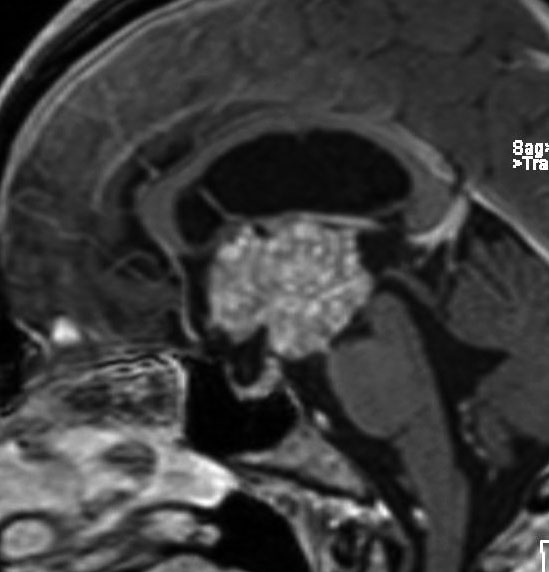

この子の症状は頭痛だけ。両親はなぜ気づかなかったのかと疑問を持ちますが,巨大になるまで症状が出ないこともあるのです。左のCTで腫瘍の周囲にバラバラと白い点状の石灰化があるので診断できます。左の視床下部から発生したクラニオでした。開頭手術しますが超高難易度です,怖いです (┯_┯) 複数回開頭手術になりましたが結果的に全摘出できています (by Dr 山本哲哉)。

嚢胞(液体が入っている袋)の部分と,腫瘍細胞が固まっている実質部分が入り交じっています。このくらいの大きさになってしまうと,下垂体機能を残すことはとても難しくなります。視神経が圧迫されて視力低下と視野障害を生じます。第3脳室が腫瘍で閉塞していて水頭症になっていますから知能の活動が低下します。

腫瘍を摘出するのに危ないのは,脳の血管の損傷です。左では白く,右では黒く線状に移っているのが太い脳動脈です。これら以外にもたくさんの細い重要な動脈が絡んでいます。

幸いこの患者さんの腫瘍は摘出できて患者さんは元気になりました。でもこのくらいのサイズになると手術がいつもうまくいくとは限りませんし重大な障害が残ることもあります。